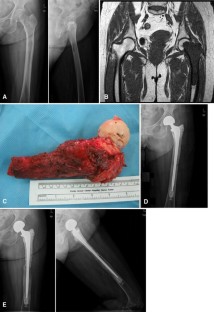

Fig. 2